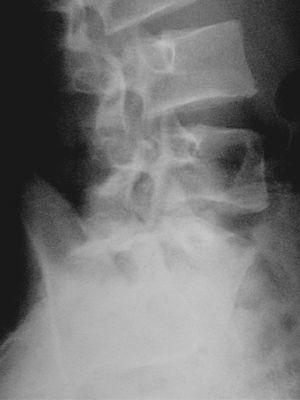

El nuevo estudio radiográfico demuestra espondilólisis L5 derecha y persistencia de integridad del hemiarco izquierdo (figs. 6 y 7). Igualmente, el estudio radiográfico dinámico demuestra establidad completa de la charnela lumbosacra (fig. 8). Por todo ello se planea el alta deportiva, aunque se le recomienda continuar un mes más el tratamiento, demorando el regreso a la práctica deportiva.

Figura 6

Figura 7